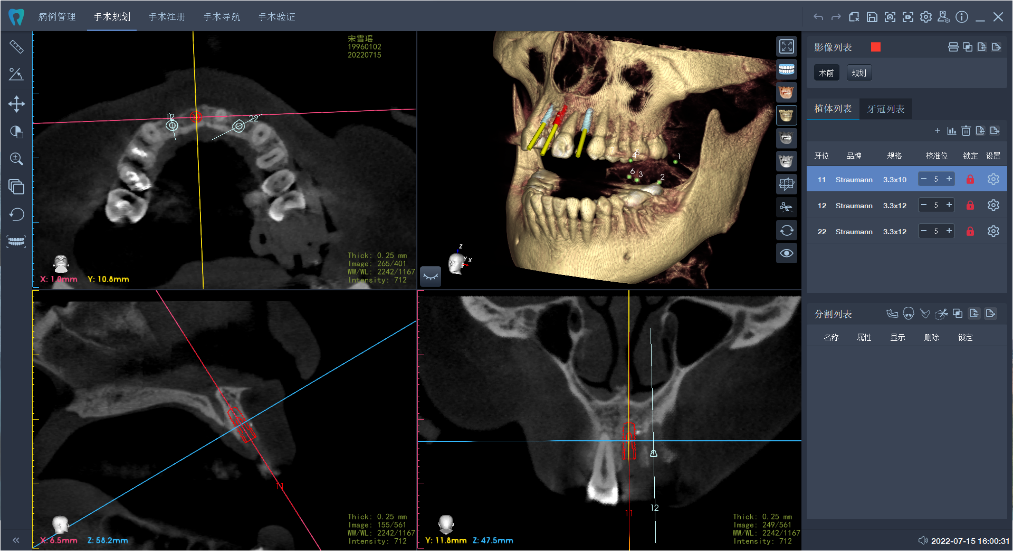

術(shù)前,醫(yī)生將患者的影像學(xué)資料導(dǎo)入機(jī)器人系統(tǒng),進(jìn)行種植體植入全過程的體外可視化模擬,這樣手術(shù)團(tuán)隊(duì)能充分了解患者牙槽骨的骨量及解剖結(jié)構(gòu)走向,更詳盡地制訂手術(shù)方案。術(shù)中,高益鳴主任、李小曼醫(yī)生共同按既定方案,在機(jī)器人全自動模式下,精準(zhǔn)標(biāo)定種植位點(diǎn)并逐級擴(kuò)孔備洞。而且,機(jī)械臂的減速區(qū)設(shè)定,讓機(jī)器人在入口時動作不會過快,“溫柔”且“迅速”地有序按照指令進(jìn)行手術(shù)。手術(shù)過程相比傳統(tǒng)方式來說縮短了近一半。如今,這位女士恢復(fù)良好。